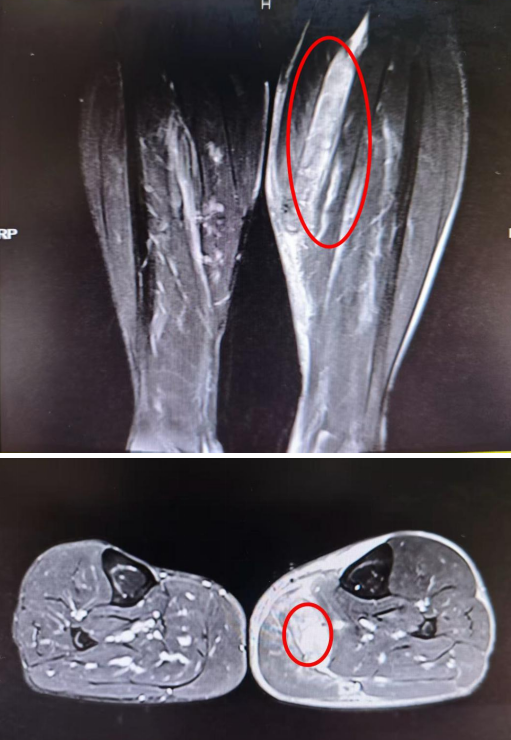

(▲核磁共振显示:腓肠肌内侧头撕裂,血肿形成。)

着急的李先生来到湖南旺旺医院骨一科就诊,经关节镜与运动损伤专科主任肖勇检查后确诊为:腓肠肌内侧头撕裂合并血肿形成。